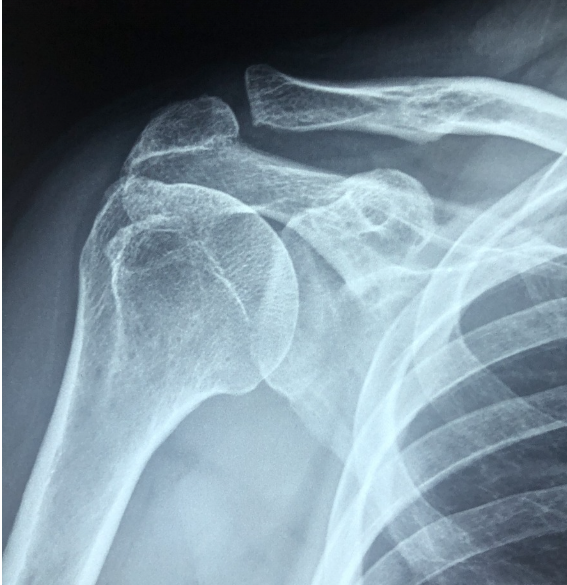

오십견은 어깨 관절을 감싸는 관절막에 염증과 유착이 생겨 발생하는 질환 입니다. 정식 명칭은 유착성 관절낭염(동결견) 으로, 어깨 관절의 가동 범위가 점점 줄어들어 일상생활에 큰 불편을 초래합니다.

오십견의 대표적인 증상은 어깨 통증과 운동 제한 입니다. 초기에는 가벼운 뻐근함으로 시작되지만, 점차 팔을 들어 올리는 것조차 힘들어질 수 있습니다.

1️⃣ 어깨 관절의 뻣뻣함과 통증

2️⃣ 팔을 위로 올리거나 뒤로 돌리기 어려움